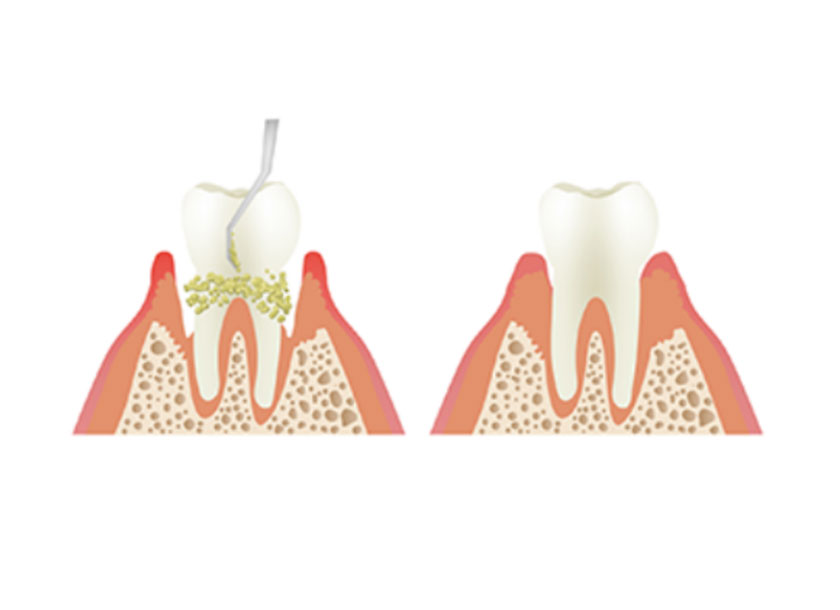

歯周病の原因となる歯周病菌は、他の細菌たちとともに『プラーク』と呼ばれる集合体の中で生息しています。

歯周病の基本治療ではまずこのプラークを徹底的に除去し、さらにお口の中を歯周病菌が住み着きにくい環境へ整えていきます。

お口の中のクリーニング(スケーリング・PMTC)

SRP(スケーリング・ルートプレーニング)

歯周病が進行すると、歯と歯ぐきの間に『歯周ポケット』と呼ばれるすき間ができます。

この歯周ポケット内にたまっているプラークや歯石を取り除いていくのがSRP(スケーリング・ルートプレーニング)という処置です。

SRPではさらに歯面を滑らかに仕上げて、プラークが付着しにくい環境へと整えていきます。